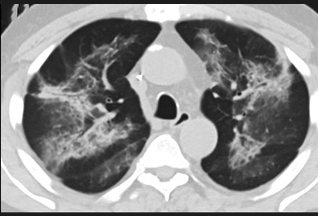

更值得注意的是,有之前应对过武汉新冠疫情的中国权威肺病专家,在查阅了60篇涉及美国“电子烟肺病”病例的研究论文,并对其中142位电子烟肺病患者的250张肺部影像图片、临床信息以及文献原文进行了仔细全面的研究后,发现这些病例中有16个更有可能是新冠肺炎的“疑诊患者”,有5个临床症状和治疗情况相对完整的患者,还被这些专家认定为了“中度可疑”。另外,这16个病例中有12个病例的发病时间,都在2020年以前。

(这4张图,是专家怀疑被误诊为电子烟肺病的其中一个病例的肺片。专家表示,他们不是仅仅通过一张影片做判断的,而是通过这4张涵盖了这名病例肺部多天变化情况的影片进行的研判,认为该病例的病程进展跟新冠更为相似)